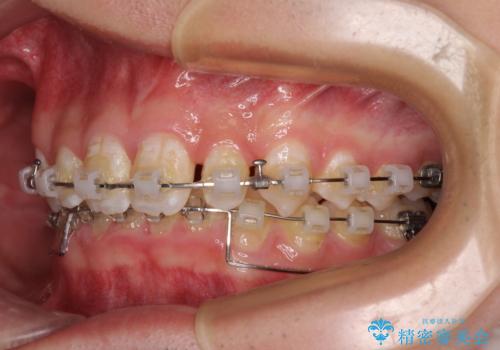

- クリアブラケット

このような咬み合わせの場合、治療期間は2年以上がかかることが一般的で、3年程度かかることもありえるケースです。

強く深い咬み合わせにより下顎装置は頻繁に脱離するため、治療期間が長くなりますが、予定通りに終了させることができました。